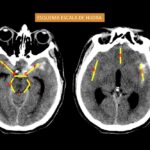

Inicialmente se dividió el patrón de la HSA en supratentorial e infratentorial y el hemisferio que ocupa la HSA. La cantidad y distribución de la hemorragia en los diversos espacios subaracnoideos, así como en los ventrículos, se analizaron en la TC de cerebro sin contraste utilizando la escala de calificación descrita por Hijdra [50]. El autor anteriormente mencionado divide el espacio subaracnoideo en 10 espacios, entre cisternas basales y las diferentes cisuras (ver Diagrama 1). La cantidad de sangre extravasada se clasificó así, 0: sin sangre; 1: escasa cantidad de sangre; 2: moderadamente cantidad de sangre; 3: abundante cantidad de sangre. La cantidad total de sangre subaracnoidea (puntuación total) fue calculada sumando las 10 puntuaciones. El rango posible fue de 1 a 30. La cantidad de sangre en los 4 ventrículos se estimaron así, 0: sin sangre; 1: sedimentación de sangre en la parte posterior del ventrículo; 2: ventrículo parcialmente lleno de sangre; 3: ventrículo completamente lleno de sangre. El total de la cantidad de sangre intraventricular (puntuación total) fue de 0-12.

Fig. 8. Esquema de escala de Hijdra, representada en una TC de cerebro sin contraste corte axial a nivel de las cisternas selar y perimesencefalica (derecha) y a nivel de la cisura de Silvio (izquierda).